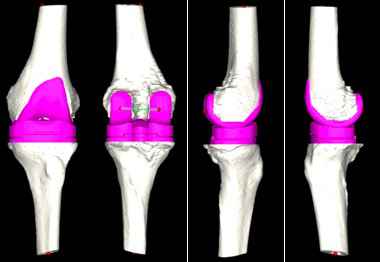

对此,张弛团队在与患者及家属充分沟通后,决定使用人工智能系统辅助置换全膝关节。专家在系统中上传患者的CT资料,人工智能便快速完成了术前规划,其模拟的假体型号及角度、位置十分精准。

人工智能术前规划模拟出精准的假体大小和位置。

“传统的全膝关节置换术极其依赖术中所见及骨科医生的临床经验,医生常需于术中反复比对以寻找最适假体大小,由于患者个体差异大、病情复杂等问题,导致全膝关节置换术后患者满意度偏低。”张弛解释说,“该患者病情复杂,通过人工智能辅助,能够在术前精准规划,帮助手术更快速、更精准的实现。”

术中运用后交叉韧带保留型的假体进行膝关节表面置换,术后复查照片精准复制了人工智能测量的结果。